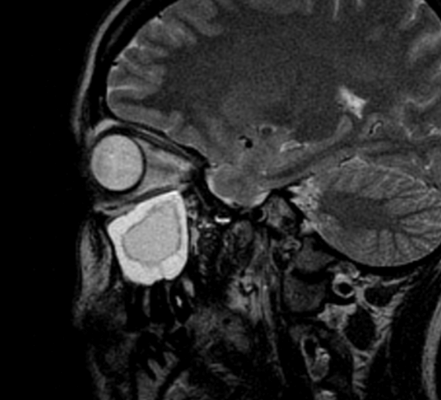

Пиоцеле (скопление гноя) задних клеток решетчатой кости

Инфекционно-воспалительные процессы слизистой оболочки носа распространяются на близлежащие ткани и провоцируют синусит. Хронические изменения предрасполагают к формированию новообразований в пазухах. Нарушения аэрации (насыщения воздухом) и дренажа полостей ведут к размножению патогенной микрофлоры с развитием гнойно-некротических изменений.

Пазухи находятся близко к внутричерепным структурам (мозг), зрительному аппарату, среднему и внутреннему уху. Без лечения острое воспаление в синусах может перейти в хроническую форму, распространиться на близлежащие ткани и вызвать серьезные осложнения.